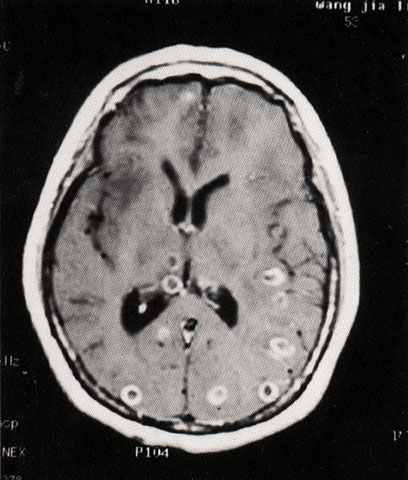

FH1050 脑囊虫病(MRI)

图  名 脑囊虫病(MRI)